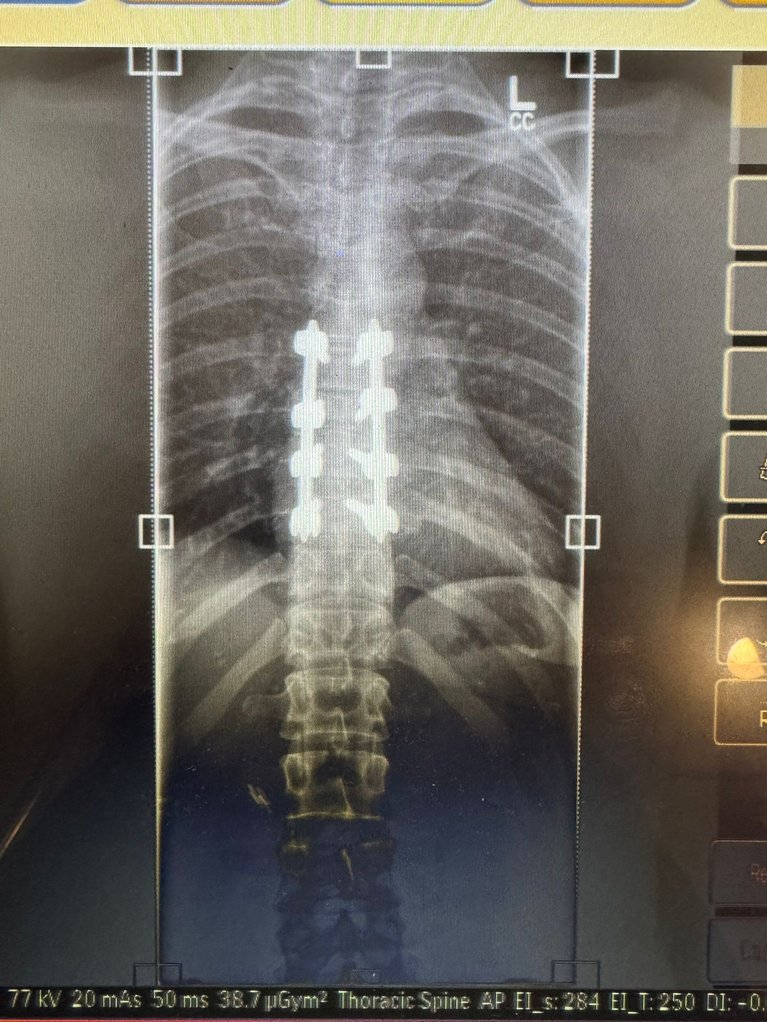

The whole crew had to wrap me up and help me down the mountain. I went to the hospital in Japan, and they found out I had an unstable fracture in my T8 and a fracture in my T9 vertebrae. It was obviously super scary. I flew back to Canada and had surgery the day after I got home—they fused my T7, T8, T9, and T10 at the hospital in Vancouver. Since then, I’ve just been focused on recovery for the rest of the winter.

BACK XRAY.JPG